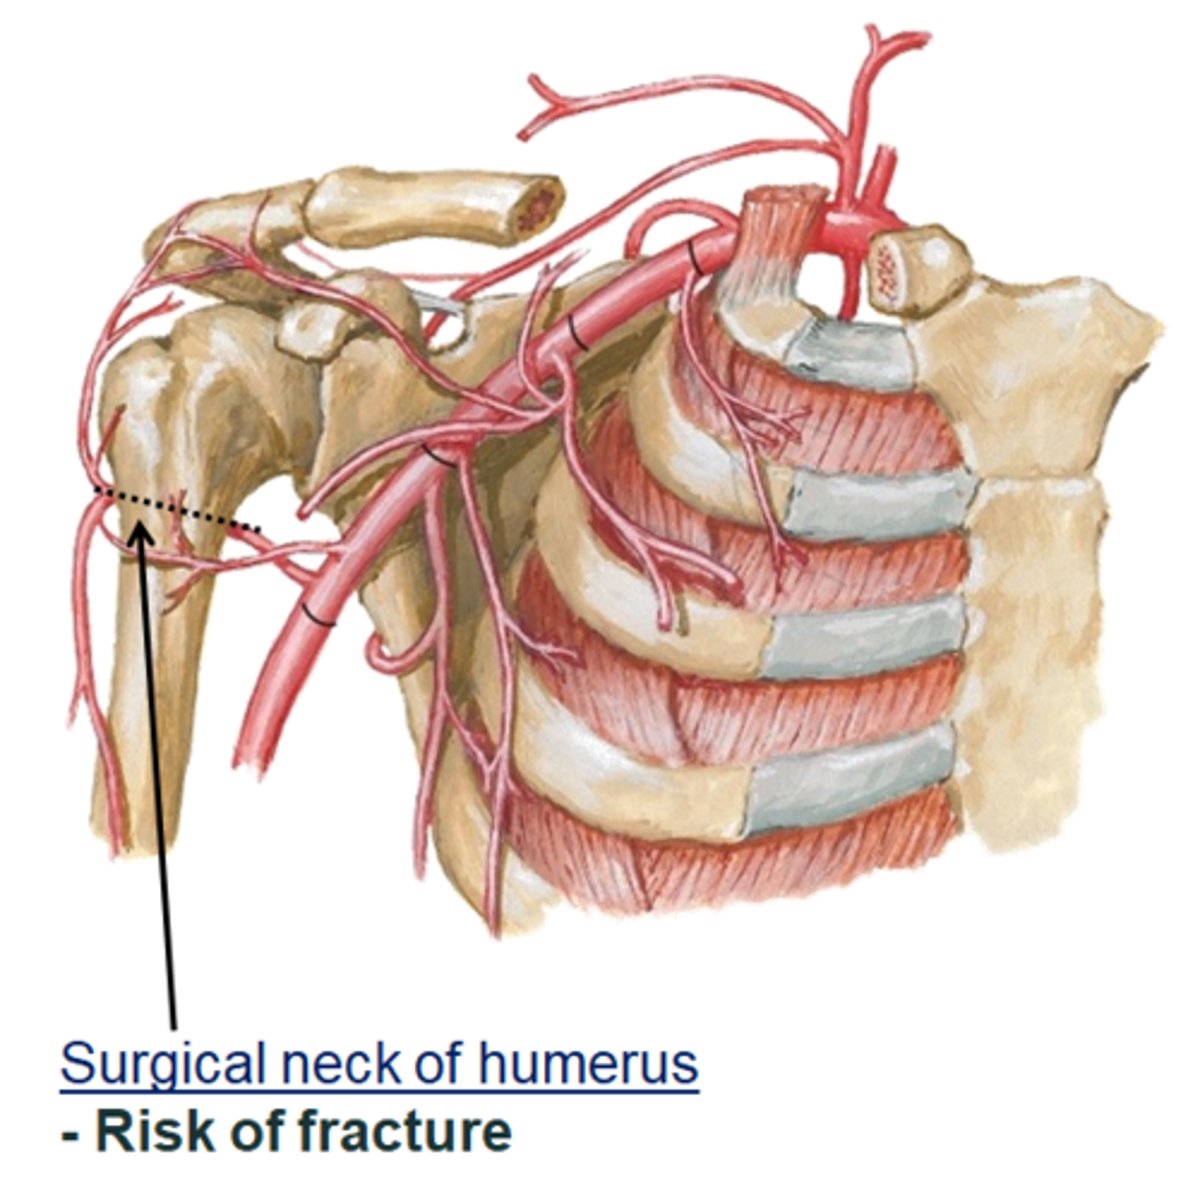

Surgical neck of humerus:

- narrow part distal to head and tubercles

- common site of fracture!!!

Clinical relevance of humerus:

axillary nerve wraps around the surgical neck. fracture of the surgical neck may damage the axillary nerve. Integrity of this nerve is tested by touching the deltoid, since the nerve provides sensory innervation to this area of the shoulder region